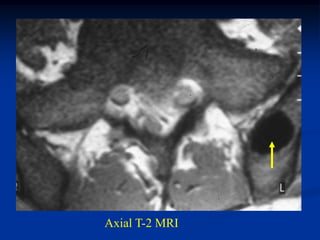

65 year female with old rh arth with multi THA’s and current

pseudoarthrosis; on coumadin and painful lytic lesion ilium

CT scan looks like metastatic hemorrhagic thyroid or renal CA

hematoma

Axial T-1 MRI shows large iliac hematoma and at biopsy

no tumor was found